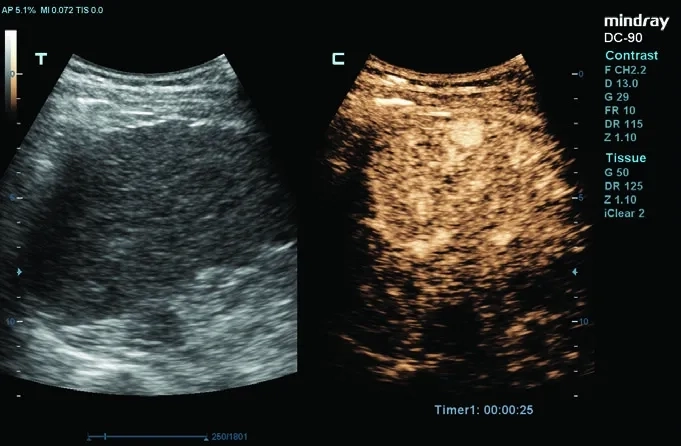

• UWN Contrast Imaging™ — ПО для исследований с контрастными веществами;